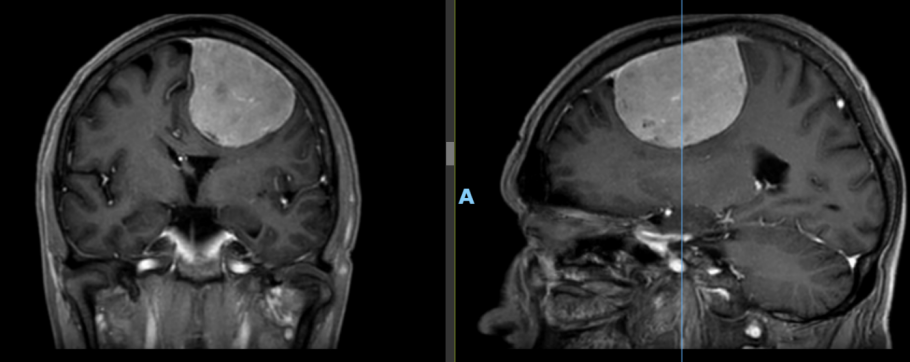

患者李大爷(化名)今年70岁,两个月前开始出现右侧胳膊麻木、活动受限等症状。经家属陪同至我院神经外科就诊,头颅磁共振检查提示其颅内存在一直径约7厘米的矢状窦旁脑膜瘤,体积巨大,病情复杂。

术后,李大爷意识迅速恢复,顺利拔除气管插管。术后第一天复查头颅CT及MRI显示术区无出血、脑组织复位良好,肿瘤切除彻底。在护理团队的精心照料下,李大爷恢复良好,肢体活动与言语功能均未受影响,近日已康复出院。